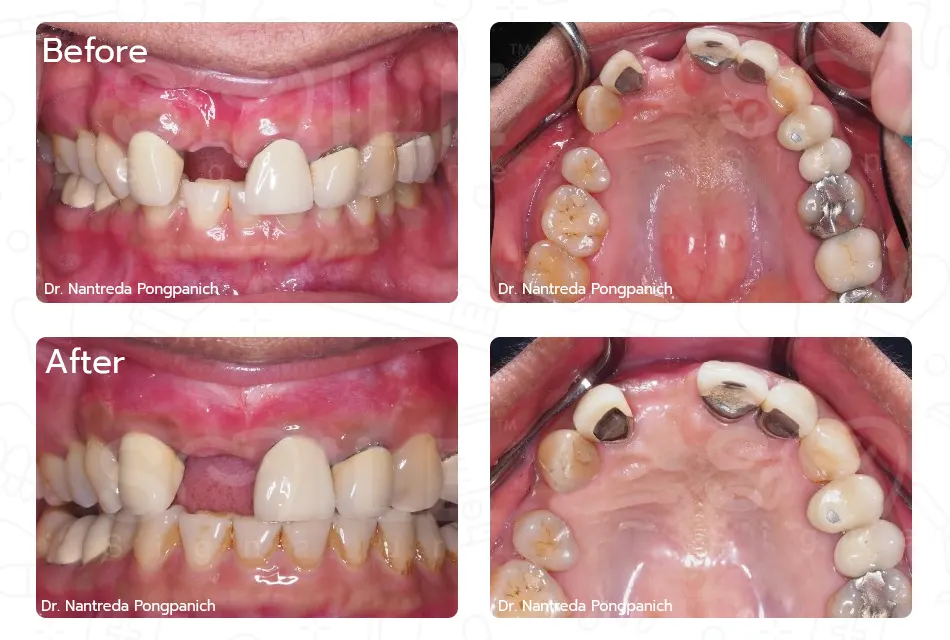

เฉพาะทางสาขาสาขาทันตกรรมรากเทียม, สาขาศัลยศาสตร์ช่องปาก และแม็กซิลโลเฟเชียล